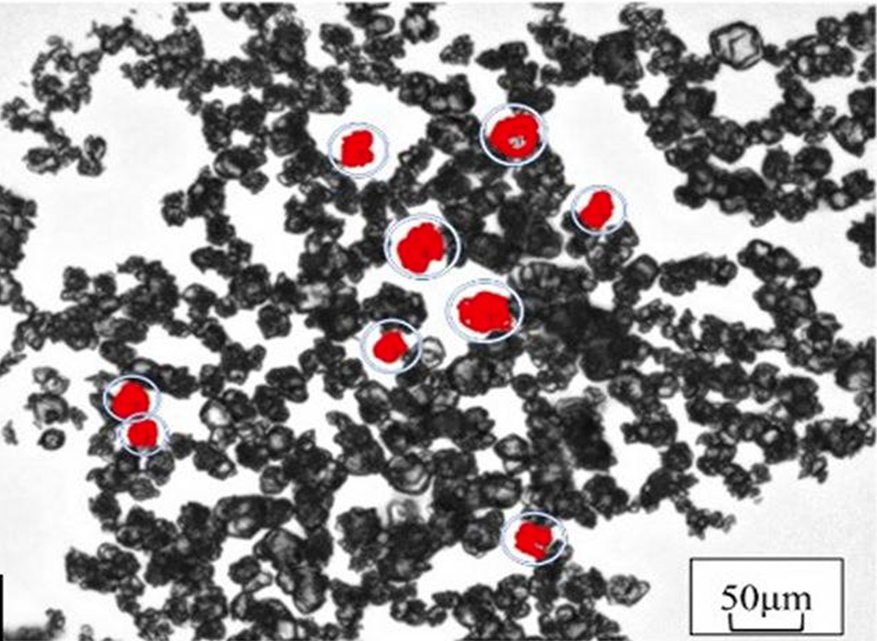

EBIR-20D :

PEO 기반

Gel-beads